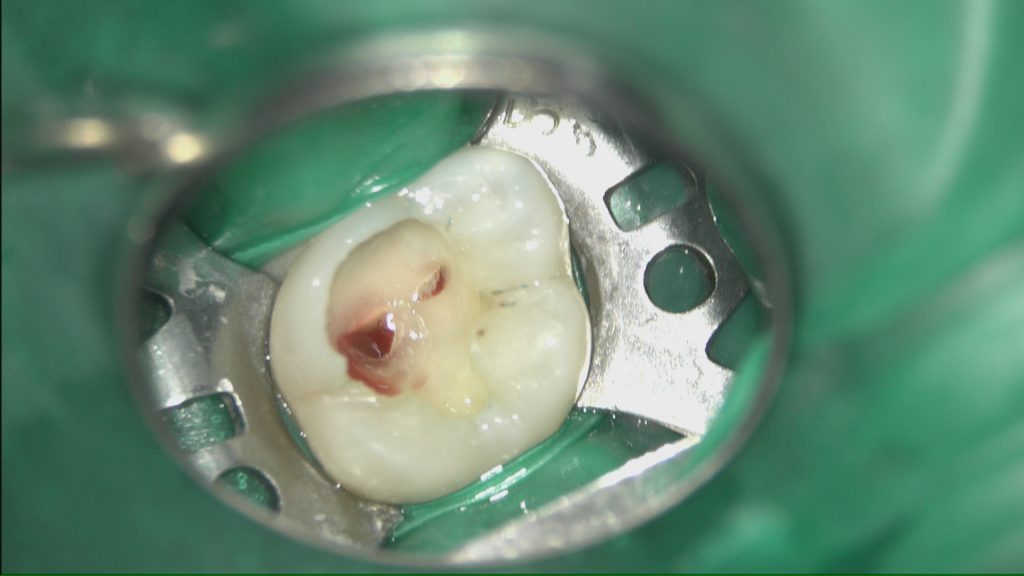

不可逆性の炎症を起こしている神経を慎重に取り除き止血確認OKの状態です。

出血の状態やマイクロスコープ下で見て除去具合を判断していきます。

MTAにてリペアして樹脂にて封鎖します。

後日、歯髄診をして状態に問題なければダイレクトボンディングかセラミックにて修復していきます。